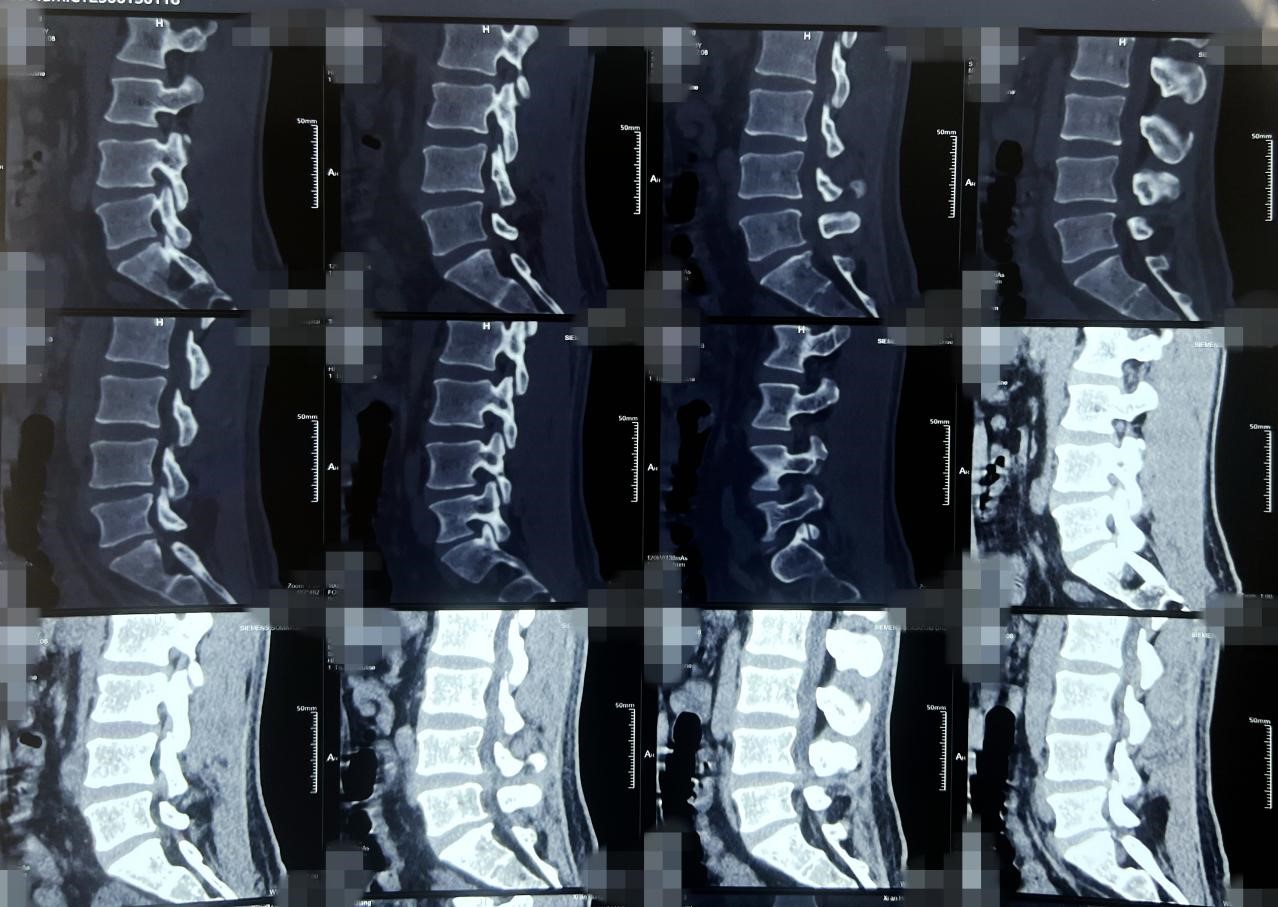

术后复查核磁

术后当天,患者术前下肢疼痛麻木症状缓解,无其他不适,复查核磁硬膜囊膨隆,减压效果满意。